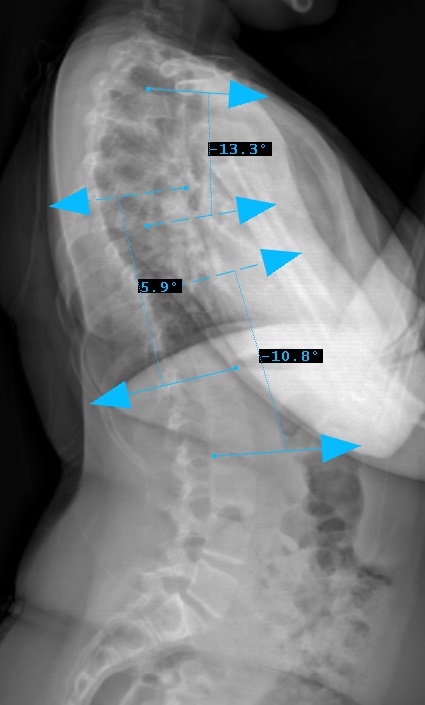

Sagittal Modifier ( - )

T5-T12 in the <10o range

Therefore, Classification is Type 2A-

Preop LAT View